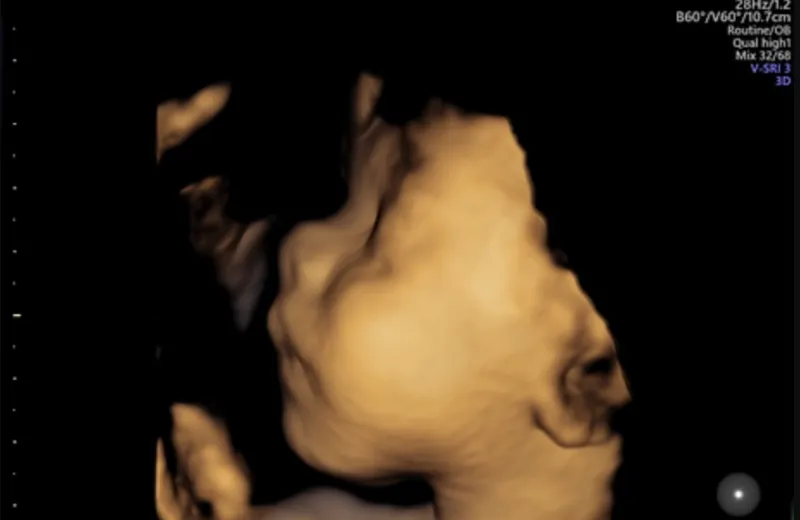

3D/4D Scanning (fra uge 26-30) — Tillægsvalg

Få 200 kr i rabat, hvis du vælger at inkludere 3D/4D scanning til din pakke. Dette har en merpris på 1.300 kr.

Se dit barn i fantastisk 3D/4D — et unikt minde for hele familien.